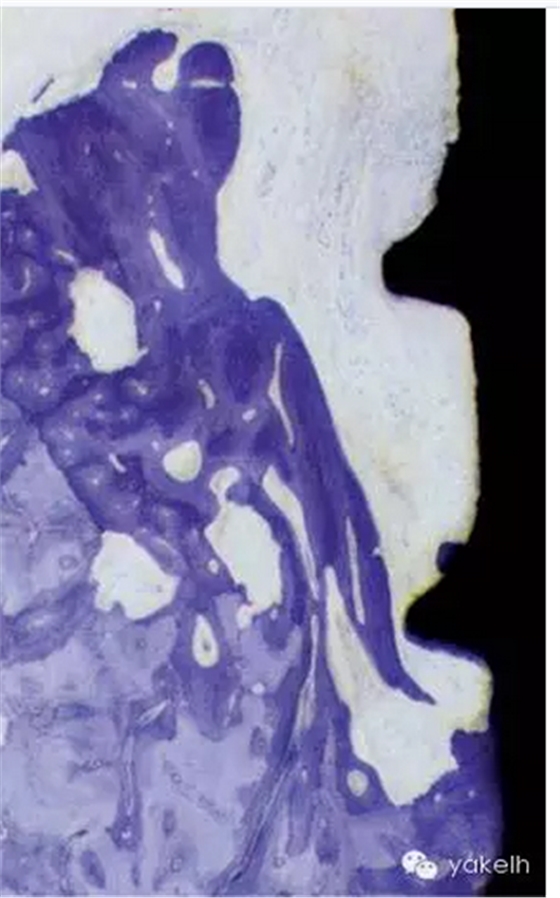

¤¤對實驗狗組織樣本的組織病理學檢查顯示,牙周位點和種植體位點炎癥病損的大小和位置明顯不同。在牙周位點,病損和牙槽骨間會被非炎癥性的結締組織區(qū)隔離,而種植體周圍組織病損在大多數情況下卻會擴展和侵入牙槽骨的骨髓腔。

¤¤我們可以得出的結論是牙周組織和種植體周圍組織的炎癥的擴散類型不同。菌斑相關的牙周炎病損會被局限在結締組織中,而種植體周圍的病損會侵入牙槽骨。與牙周組織相反,在種植體周圍組織,進展的、菌斑相關的病損似乎很難被局限以消除,可以擴展到邊緣的骨組織內,進一步發(fā)展最終導致種植體失敗。用狗模型進一步研究,觀察不同時期的組織破壞,已經證實這個結論。